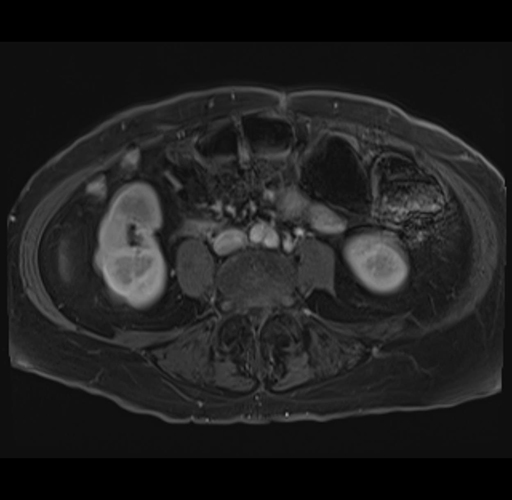

MRI T1

Imaging analysis